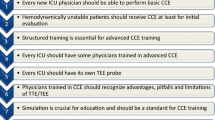

Echocardiography has become readily accessible to critical care physicians now and equipment is even been designed specifically for use in acute and critical care environments. The most important barrier to a more widespread implementation of this technique today, however, is the lack of training and experience. Indeed, proficiency is an absolute requirement for echo-based decision-making to positively impact on patient outcome.

Echocardiography has become an indispensable tool in the management of critically ill patients with severe cardiorespiratory conditions. It has the potential to become a game changer in ICU but current studies do not yet indicate a beneficial effect on outcome. It appears that structured training and certification in basic echocardiography are an absolute necessity to catalyze the widespread adoption and to guarantee the optimal use of ultrasound in the care of critically ill patients.

Although numerous reports indicate the superior value of critical care echocardiography for cardiopulmonary assessment and diagnosis, beneficial effects on patient outcome are yet to be demonstrated [7]. In fact, the widespread adoption of ultrasound-based imaging outside traditional professional specialisms has raised concerns about potential harm associated with the lack of proficiency and inappropriate use of the technology. For this reason, high priority should be given to the implementation of training programs ensuring that learners are capable of demonstrating proficiency in echocardiographic image acquisition and interpretation in the clinical context of critical care and perioperative medicine [8,9,10].